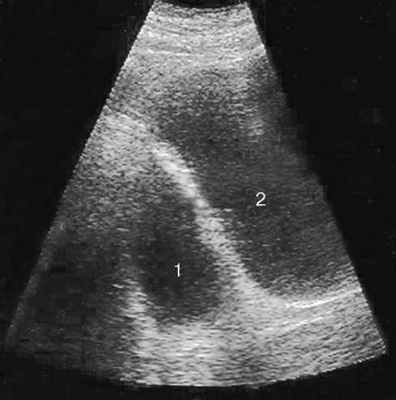

Диагноз устанавливается на основании УЗИ (рис. 5.35), цистографии (рис. 5.36) и цистоскопии (рис. 20, см. цв. вклейку).

Рис. 5.35. Трансабдоминальная сонограмма. Дивертикул (1) мочевого пузыря (2)